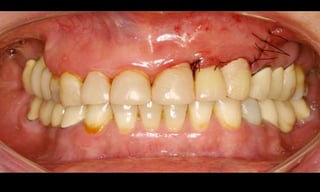

10-10-2005

Novembro de 2005

24-01-2006

Cone Morse